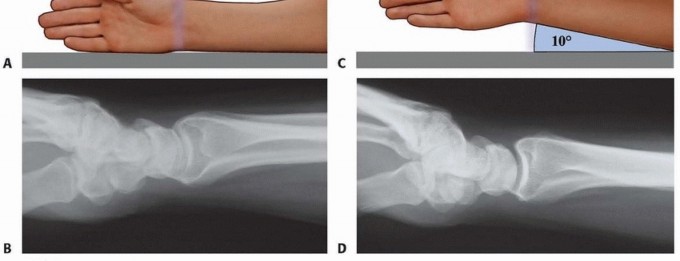

### FIG 4 • A. Positioning for standard lateral radiography. B. Standard lateral radiograph. C. Positioning for 10-degree lateral radiography. D. Ten-degree lateral radiograph. Note the improved visualization of the articular surface of the base of the scaphoid facet and the entire lunate facet. Injuries from a high-energy mechanism present as complex comminuted fractures of the articular surface with extension into the radial/ulnar shaft ( FIG 3I). ## IMAGING AND OTHER DIAGNOSTIC STUDIES Posteroanterior (PA), standard lateral ( FIG 4A,B), and 10-degree lateral views are routine views for radiographic evaluation of the distal radius. The 10-degree lateral view (FIG 4C,D) clearly visualizes the ulnar two-thirds of the articular surface from the base of the scaphoid facet through the entire lunate facet. Oblique views may also be helpful for evaluating the injury. The radiographic features of distal radius fractures include the following 8: Carpal facet horizon ( FIG 5A,B). This is the radiodense horizontal landmark that is used to identify the volar and dorsal rim on the PA view. If the articular surface has palmar tilt, the x-ray beam is tangential to the subchondral bone of the volar portion of the lunate facet, with the result that the carpal facet horizon identifies the volar rim. However, if the articular surface has displaced into dorsal tilt, the x-ray beam becomes tangential to the subchondral bone of the dorsal portion of the lunate facet instead, and the carpal facet horizon identifies the dorsal rim (not shown). The carpal facet horizon corresponds to the portion of the articular surface visualized on the 10-degree lateral x-ray projection. Teardrop angle (normal 70 ± 5 degrees; FIG 5C,D). The teardrop angle is used to identify dorsiflexion of the volar 79 rim of the lunate facet. Depression of the teardrop angle to a value less than 45 degrees indicates that the volar rim of the lunate facet has rotated dorsally and impacted into the metaphyseal cavity (axial instability pattern of the volar rim). This may be associated with axial and dorsal subluxation of the carpus. Restoration of the teardrop angle is necessary to correct this type of malreduction.